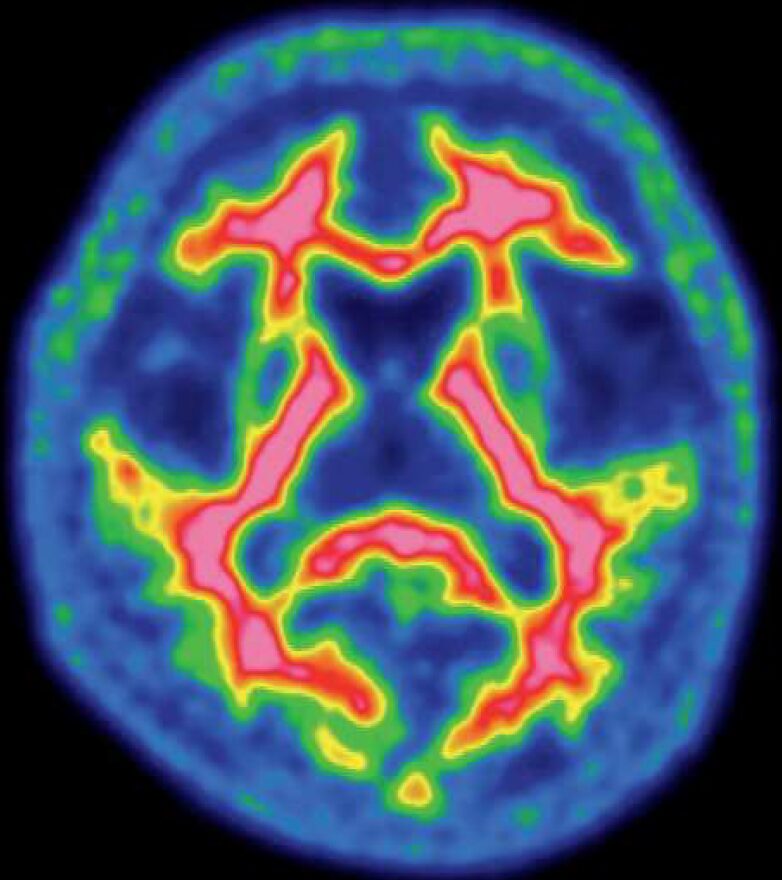

正常の脳核医学画像を示す。使用した放射性医薬品はどれか。

✔ 画像の特徴を読み解く

提示された画像を見ると、脳の表面(大脳皮質)が均一に光っているわけではなく、その内側にある大脳白質に沿って、脳溝の形を縁取るように放射能が集まっているのが分かります。

これは、正常な脳におけるアミロイドPETトレーサーの分布として、典型的なパターンです。

5.¹⁸F-フルテメタモル

- ✅ 正解

- アルツハイマー病の原因物質であるアミロイドβプラークを可視化するPET薬剤です。

- 正常な脳では、このように大脳白質に沿った非特異的な集積パターンを示します。

- 画像はアミロイドPETの正常像。使用薬剤はアルツハイマー病の原因物質を可視化する¹⁸F-フルテメタモルである。

- 正常なアミロイドPETは、大脳白質に沿った非特異的集積が特徴的なパターン。